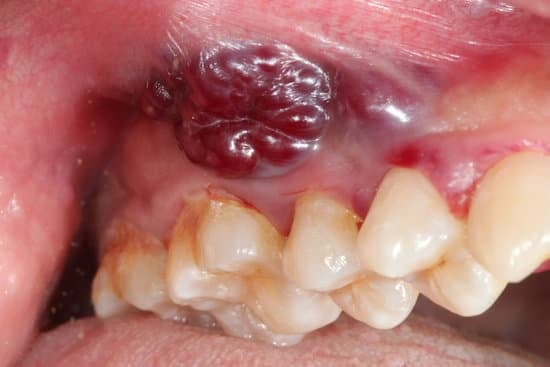

구강암은 입 안의 다양한 부위에서 발생하는 악성 종양을 말합니다.

구강암은 혀, 입술, 잇몸, 뺨 안쪽, 입천장, 입 바닥, 그리고 편도와 같은 구조에서 발생할 수 있습니다.

입 안의 궤양 또는 덩어리: 2주 이상 지속되는 통증 없는 궤양이나 덩어리가 있을 수 있습니다.

입술이나 입 안의 붉거나 흰 반점: 비정상적인 색소침착이 발생할 수 있습니다.

출혈: 원인 없이 입 안에서 출혈이 발생할 수 있습니다.